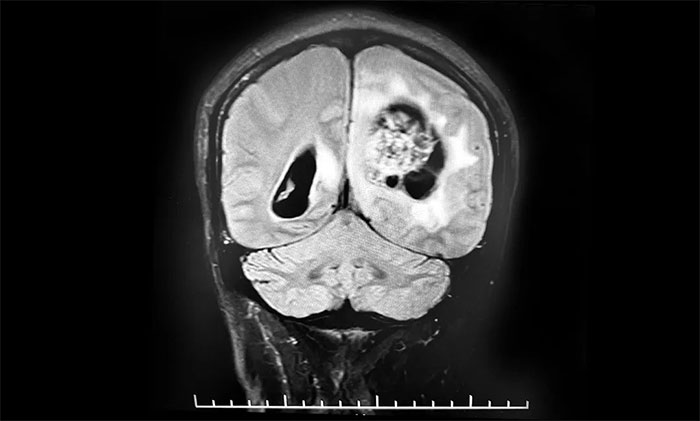

頭顱MRI平掃+增強+DWI+MRA提示,左側頂枕葉巨大腫瘤伴局部瘤卒中,幕上腦室系統(tǒng)、腦干受壓變形,中線結構右移19mm,大腦鐮下疝形成。李士其教授等專家團隊會診指出,患者腦內(nèi)巨大占位,性質(zhì)不明,并且患者已經(jīng)發(fā)生腦疝昏迷,生命危在旦夕,應盡快進行手術治療,挽救患者生命,同時明確病理診斷。

▲ 左側頂枕葉巨大腫瘤伴局部瘤卒中